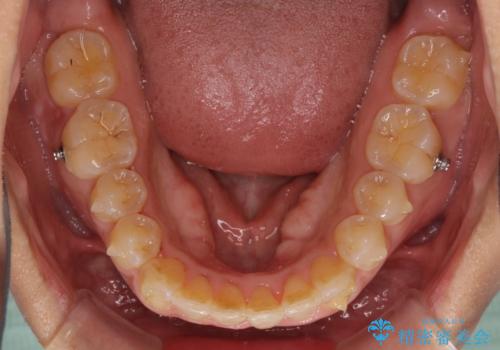

インビザラインによる狭窄歯列の拡大矯正

- 矯正装置

- インビザライン

- 2年2ヶ月

治療途中で関西に転勤となってしまったため、東京に出張で来るタイミングに合わせて治療を進めることになりました。そのため、治療期間が長くなってしまいましたが、無事に仕上げることができました。